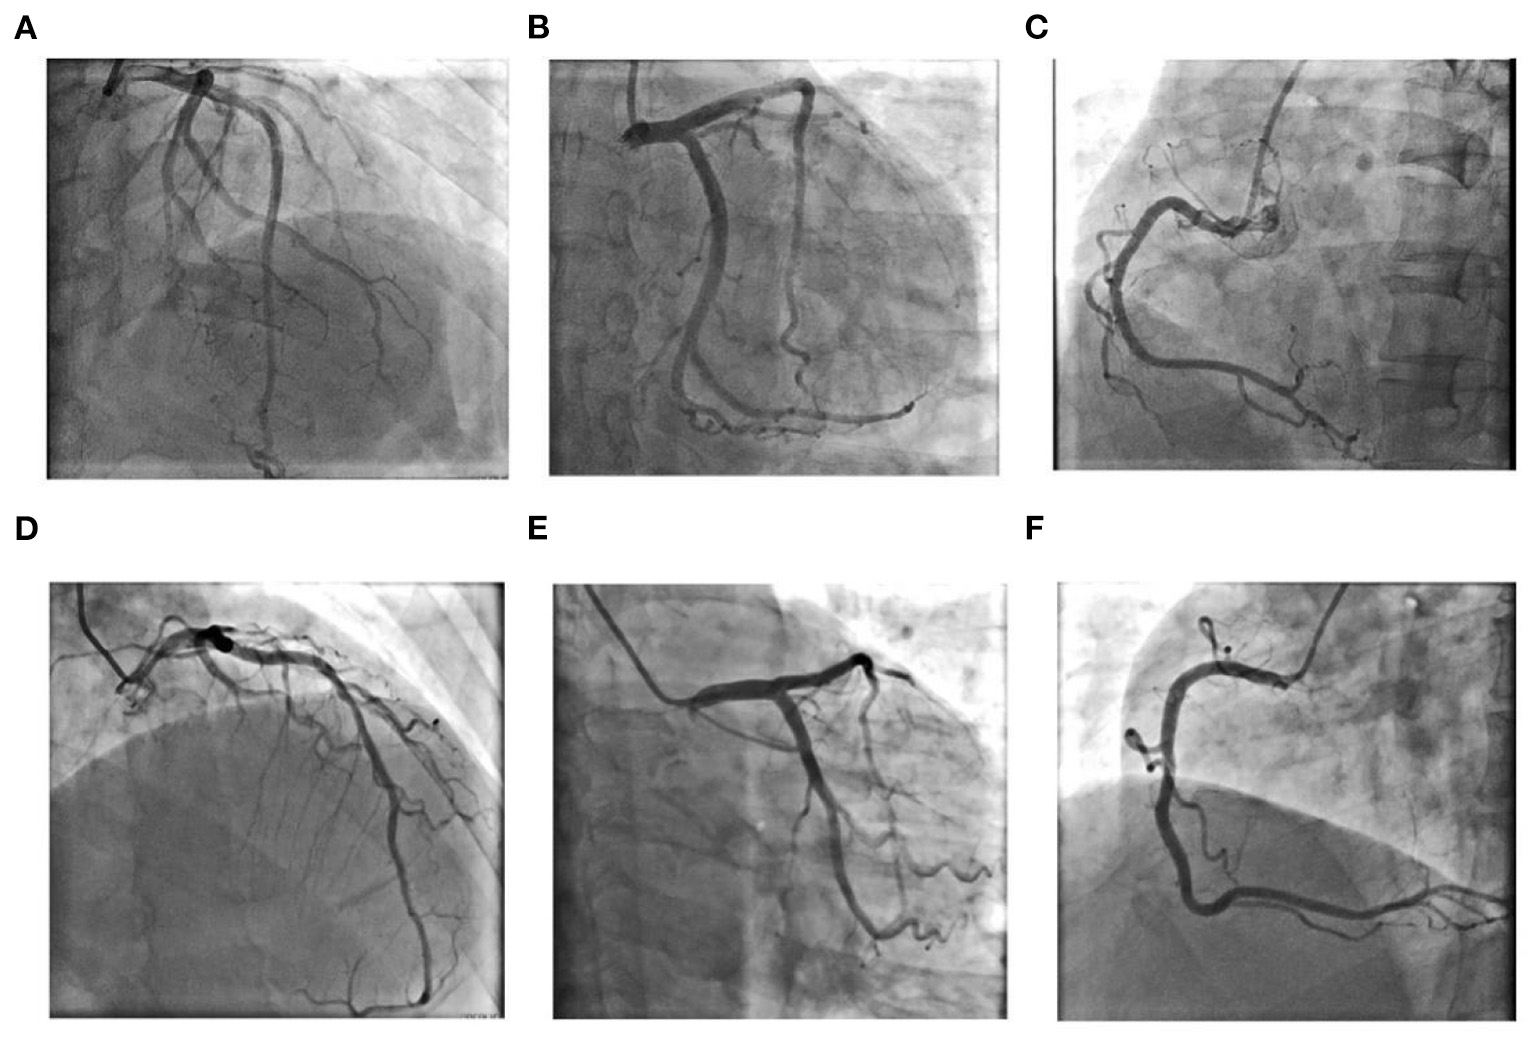

Figure 2

Coronary angiography results for Case 1 (A–C): (A) Left coronary artery: Cranial 30°; (B) Left coronary artery: Caudal 30°; (C) Right coronary artery: Left anterior oblique 45°; Coronary angiography results for Case 2 (D–F): (D) Left anterior oblique 30°+ Cranial 30°; (E) Left coronary artery: Caudal 30°; (F) Right coronary artery: Left anterior oblique 45°.

The admission electrocardiogram showed a right bundle branch block (Figure 1A). Urgent coronary angiography excluded coronary artery disease (Figures 2A–C); therefore, transthoracic echocardiography (TTE) with strain analysis revealed diffuse left ventricular hypokinesia and increased thickness of the mid-ventricular septal wall (septal wall 13 mm; inferior wall 11 mm), and markedly reduced LV ejection fraction (LVEF 30%) (Figures 3B,D). Based on all these clinical and laboratory data, fulminant myocarditis was diagnosed, and treatments were immediately initiated with an intra-aortic balloon pump, which elevated the systolic blood pressure from 95 to 110 mm Hg and heart rate reduced from 100 to 85 bpm; intravenous drip of methylprednisolone (400 mg intravenous drip on the first day and then 200 mg per day for 4 more days) and intravenous immunoglobulin 20 g per day for 5 days. After these treatments, the patient's circulation stabilized and gradually recovered. On day 5, cardiac magnetic resonance (CMR) was performed, and the results revealed a corresponding extensive myocardial edema and necrosis with predominant subepicardial/mid-ventricular septal distribution highly suggestive of a myocarditis pattern (Figures 3G,H). Additionally, late gadolinium enhancement imaging in different positions detected massive myocardial necrosis in the medial septum, thinning of the lateral wall of the myocardium, and fibrosis. Ventricular septal myoedema was observed on T1 mapping, and the value of myocardial T1 was significantly increased (1,364 ms, Figure 3J). Furthermore, endocardial biopsy was performed, and histological analysis showed mildly increased cardiomyocyte diameter with some perinuclear halos and dysmetric and dysmorphic nuclei, interstitial edema with lymphocytic aggregates, myocyte necrosis, and focal areas of fibrosis were observed (Figure 3L). All these results helped in establishing the final diagnosis of fulminant myocarditis, which is associated with the inactivated SARS-CoV-2 vaccination.